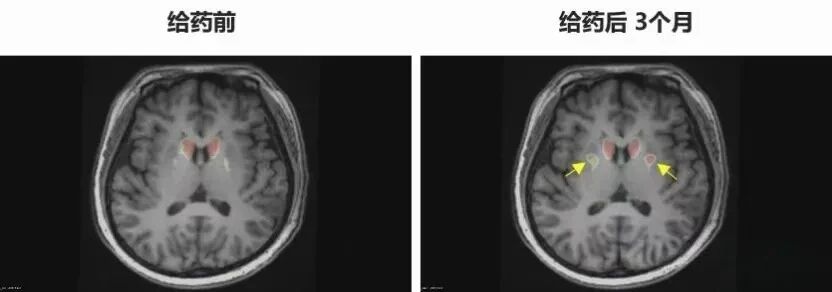

在神经系统疾病领域,挑战传统的神经退行性疾病看到了希望。一位37岁的遗传型帕金森病患者李女士,曾因传统药物疗效减退并出现严重的“开关现象”而备受折磨。今年6月,她在中国科学技术大学附属第一医院接受了基于诱导多能干细胞技术分化的多巴胺能神经前体细胞移植。术后仅三个月,她的运动症状显著改善,“关期”消失,行动恢复自如,表情也变得自然,实现了令人瞩目的“功能性治愈”。这为阿尔茨海默病、帕金森病等患者照亮了前路。